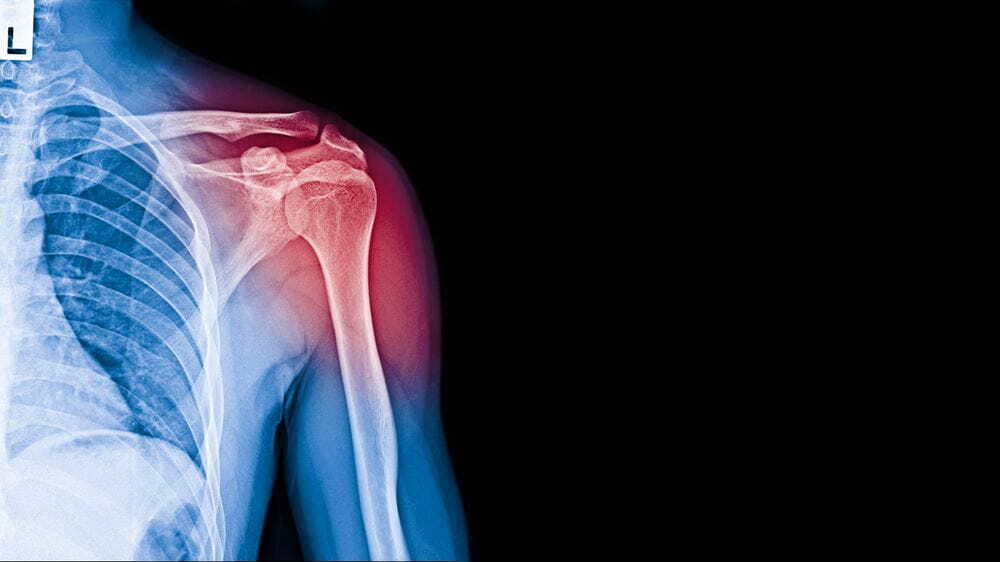

사고로 어깨뼈가 골절되었을 때, 관련된 입원 기간, 수술 후 물리치료 및 도수치료 비용, 그리고 실비보험 적용 여부에 대해 알아보겠습니다. 어깨 골절은 예상치 못한 상황에서 찾아올 수 있으며, 대비하기 어려운 사건입니다. 저 또한 몇 년 전에 어깨뼈 골절로 인한 치료를 받은 적이 있습니다. 이 글에서는 어깨뼈 골절 치료와 관련된 주요 내용을 다룰 것입니다.

어깨뼈 골절의 입원 기간은 다양하며 상황에 따라 다를 수 있습니다. 일반적으로 어깨 골절의 경우 상완골 골절로 분류되며, 핀고정 수술이 필요한 경우 보통 1주에서 2주 정도의 입원 기간이 필요합니다. 그러나 교통사고나 다른 상황으로 어깨뼈 골절이 더 복잡한 경우에는 입원 기간이 더 길어질 수 있습니다. 따라서 개별 환자의 상태와 치료 방법에 따라 입원 기간이 결정됩니다.

어깨뼈 골절 수술 후, 입원 중에는 주로 진통제가 투여되어 통증을 관리합니다. 이로써 입원 중에는 통증이 그리 심하지 않게 느껴질 수 있습니다. 상완골 골절의 경우 핀고정 수술이 주로 시행되며, 수술 후에는 상완골의 고정이 유지됩니다.